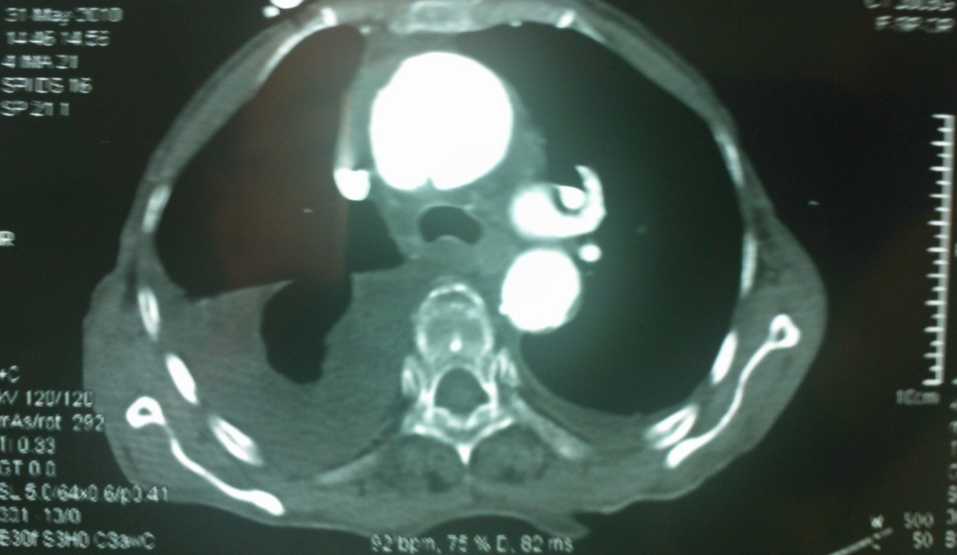

我们早期曾遇到一例升主动脉夹层治疗失败的病例(因失败未留存完整影像),但事后复盘发现,根本原因在于对主动脉三维解剖认知不足。当时采用预开窗技术,支架释放后发生近端移位和远端扭转,导致左颈总动脉与头臂干被遮蔽,最终需紧急补救性支架+两次搭桥手术。

全麻下双上肢穿刺,右股动脉切开,左上肢路径造影,右上肢进保护性导丝,对支架预开窗后植入升主,因破口较大,支架近端掉入破口,远端扭转遮蔽左颈总动脉及头臂干,窗口对破口,再次植入一枚38-80支架,封住近端破口后,以8*60支架开放右侧头臂干,6*10人工血管行右锁骨下-左颈总搭桥,取颈前静脉行左椎动脉-人工血管搭桥,之后造影,头臂动脉均通常,术后约2小时患者清醒。